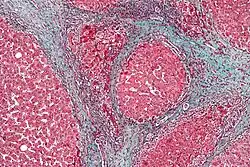

Durch den chronischen Ablauf von Untergang und Regeneration des Lebergewebes entsteht eine gestörte Gewebearchitektur mit knotigen Veränderungen. Zusätzlich bildet sich übermäßig Bindegewebe (Fibrosierung). Diese narbigen Areale können mehr als 50 % des gesamten Gewebes einer zirrhotischen Leber einnehmen. Dadurch ist die Durchblutung der Leber gestört, im Bereich der Pfortader staut sich das Blut vor der Leber (portale Hypertension).

Der Pathologe unterscheidet nach dem äußeren Erscheinungsbild des Organs die mikronoduläre, die makronoduläre und die gemischtknotige Zirrhose. Die Leber schrumpft („Schrumpfleber“), ihre Oberfläche wird runzlig und knotig. Mikroskopisch lassen sich aktive oder floride (d. h. voranschreitende) und inaktive Zirrhosen unterscheiden. Die Vorstufe der Leberzirrhose ist die Leberfibrose.